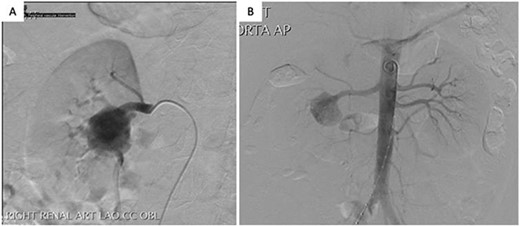

A 41-year-old male presented to his primary physician with a history of hypertension and was found to have a large right RAA on duplex ultrasound. He had a smoking history of 20 pack-years and denied any history of abdominal pain, trauma or systemic illness. CT angiography demonstrated a 32 mm fusiform RAA at the hilum of the right kidney, with multiple branches arising from it. His left renal artery appeared normal. He underwent a diagnostic catheter angiogram, which revealed a stenotic web in the right main renal artery and confirmed multiple segmental branches originating from the aneurysm (Fig. 1). Because of the number of branches, endovascular stenting or coiling was not possible without sacrificing a significant proportion of the kidney. Given the potential diagnosis of fibromuscular dysplasia in this patient, preservation of the kidney was important because of the risk of future involvement of the left renal artery. The patient was therefore worked up for an open ex vivo aneurysm repair and heterotopic autotransplantation.

Arterial phase digital subtraction angiography: A) Selective run demonstrating a large RAA arising from the right renal artery bifurcation and involving segmental arteries. B) Aortogram demonstrating both renal arteries.